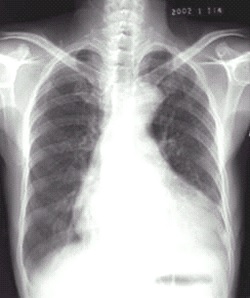

03卷-4.病史:女性,73岁,血压升高10年,心悸、头晕、乏力2周。诊断(本题满分2.00分)

A.梨形心

B.靴形心

C.普大型心脏

D.正常心脏

本题答案:B

题目解析:【该题针对“X线-心脏增大(二尖瓣型、主动脉型和普大型)”知识点进行考核】